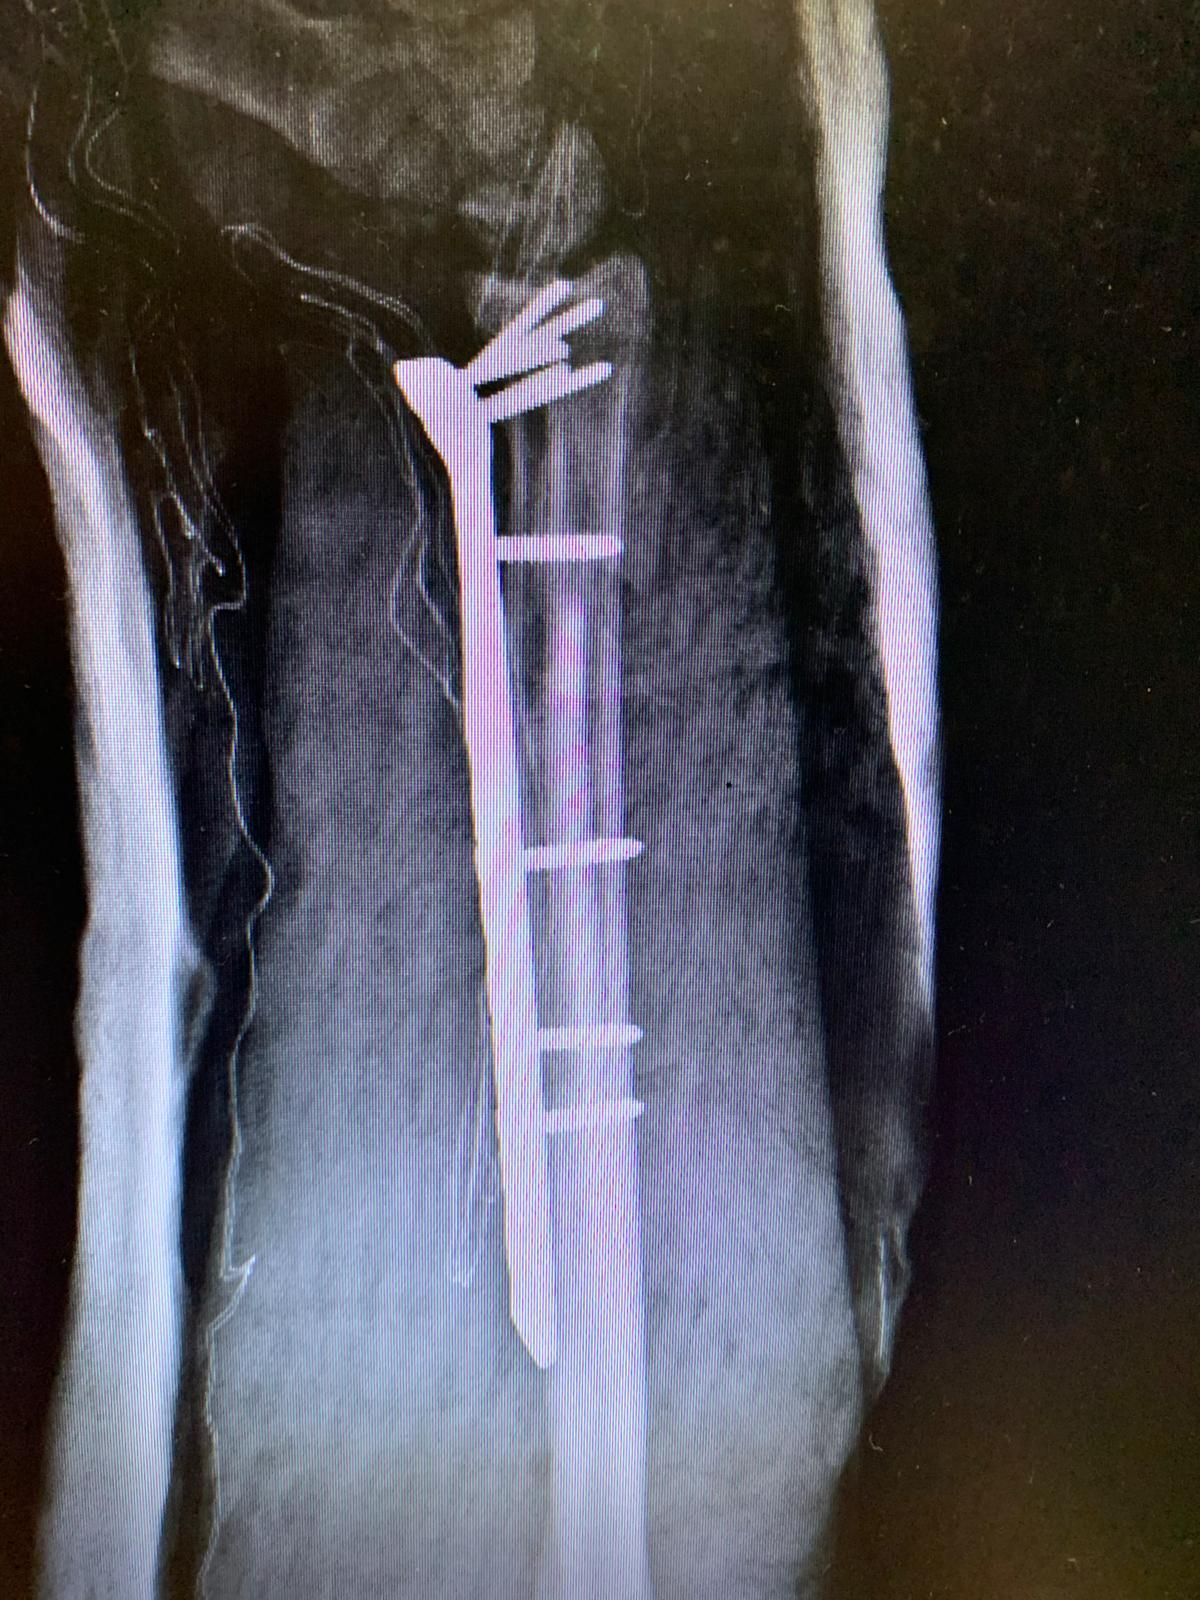

Traumatologia adulta e pediatrica

La traumatologia rappresenta un ambito fondamentale dell’attività specialistica, rivestendo un ruolo cruciale nella cura e nella riabilitazione dei pazienti colpiti da eventi traumatici. La gestione delle

lesioni traumatiche dell’apparato muscolo-scheletrico si estende a una vasta gamma di condizioni, che comprendono traumi articolari, fratture di varia gravità e lesioni che interessano sia gli arti superiori che quelli inferiori. Grazie a un’esperienza ospedaliera consolidata, i professionisti sono in grado di affrontare non solo le urgenze traumatiche, che richiedono un intervento rapido e preciso, ma anche la gestione degli esiti post-traumatici, ponendo particolare attenzione al recupero funzionale e al miglioramento della qualità della vita dei pazienti. L'approccio multidisciplinare e l'uso di tecnologie avanzate sono cruciali per garantire risultati ottimali.